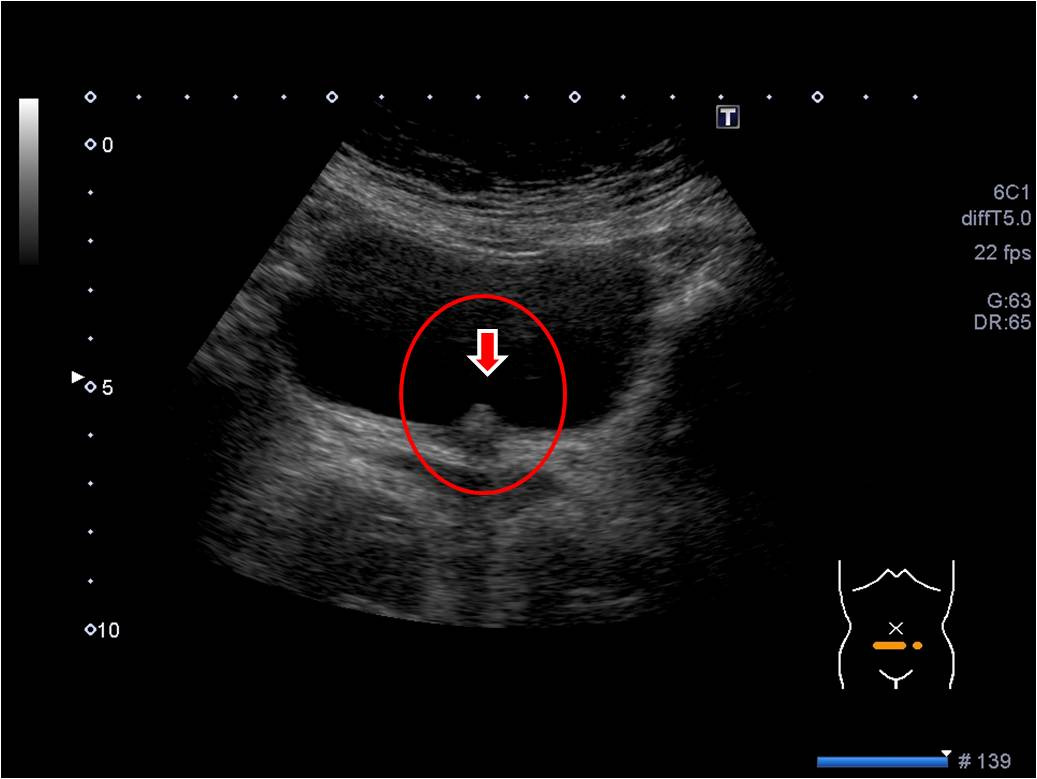

복부 초음파 검사는 인체 내부를 절개하지 않고도 간, 담낭, 췌장, 신장 등 주요 장기의 상태를 실시간으로 확인할 수 있는 대표적인 영상 검사입니다. 방사선 노출이 없고 비교적 간단하게 시행할 수 있기 때문에 건강검진이나 질병 진단 과정에서 매우 널리 활용되고 있습니다.

복부 초음파는 복부 장기의 구조적 변화, 종양, 염증, 결석 등을 확인하는 데 매우 유용하며, 장기별로 복부 초음파로 알 수 있는 것(질환)이 다르게 나타납니다.

단순히 “이상 여부”를 보는 수준이 아니라 병변의 크기, 위치, 진행 정도까지 판단할 수 있기 때문에 진단적 가치가 높습니다.

담낭은 초음파로 가장 잘 관찰되는 장기 중 하나로, 결석 여부 확인에 특히 효과적입니다.